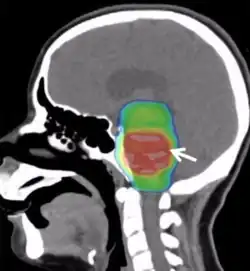

.png)

Conventional radiotherapy, limited to the involved area of tumour, is the mainstay of treatment for DIPG. A total radiation dosage ranging from 5400 to 6000 cGy, administered in daily fractions of 150 to 200 cGy over 6 weeks, is standard. Hyperfractionated (twice-daily) radiotherapy was used previously to deliver higher radiation dosages, but did not lead to improved survival. Radiosurgery (e.g., gamma knife or cyberknife) has a role in the treatment of DIPG and may be considered in selected cases.